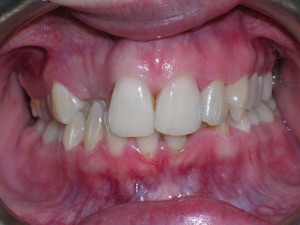

This case was of a young lady who desperately wanted Invisalign, but had been told it was not possible. There was not one, but two teeth that had come in toward the roof of the mouth.

Needless to say, we were both quite happy with the outcome. Using elastics we were able to push back the back teeth and create space for the two teeth stuck behind.